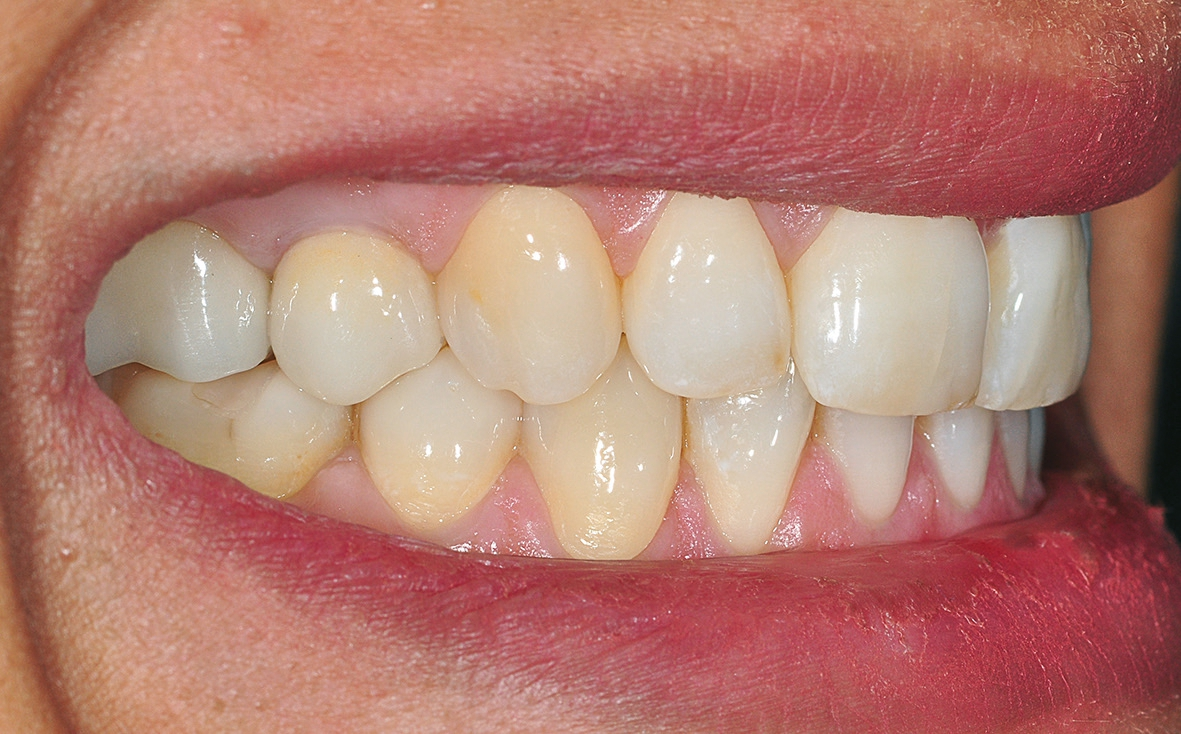

Nach einer komplikationsfreien Einheilzeit von vier Monaten konnte mit der Herstellung des definitiven Zahnersatzes begonnen werden. Hier entschied man sich konsequent für monolithische Kronen aus Lithiumdisilikat, um das Chippingrisiko so gering wie möglich zu halten [12]. Im Zuge der Implantatversorgung wurde nun auch – wie geplant – die metallkeramische Krone an 16 geschlitzt, entfernt und der Stumpf nachpräpariert. Implantatkopf und Zahnstumpf wurden daraufhin zusammen mit A-Silikon analog abgeformt. Für die geschlossene Abformung wurde die Abformkappe (impression.transfer) auf dem Implantatkopf positioniert. Ein deutliches Einrasten signalisierte den lagestabilen Sitz. Für die Modellherstellung rastete das Implantatanalog (lab. replica) ebenso in die integrierte Abformkappe ein. Nach der Herstellung des Meistermodells konnten die beiden Kronen im digitalen Workflow CAD/ CAM-gestützt gefertigt werden. Nach Ausarbeitung, Bemalung und Glasur waren die beiden Kronen für die definitive Zementierung bereit. Die klinische Einprobe der Restaurationen verlief erfolgreich, sodass die Kronen nacheinander mit selbstadhäsivem Befestigungskomposit eingegliedert werden konnten.

Aber auch bei einem nachträglichen Bindegewebstransplantat zur gingivalen Korrektur bietet ein einteiliges, spaltfreies Implantat aus gewebefreundlichem Zirkondioxid womöglich bessere Chancen auf eine zufriedenstellende rote Ästhetik als zweiteilige Titanlösungen. Die Patientin war in diesem Fall mit dem ästhetischen Erscheinungsbild und der Funktionalität ihrer neuen Versorgungen eineinhalb Monate nach der definitiven Eingliederung absolut zufrieden.